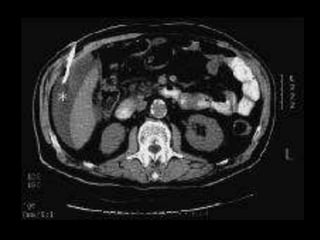

• CT scan

• CT scan abd

• CT abd